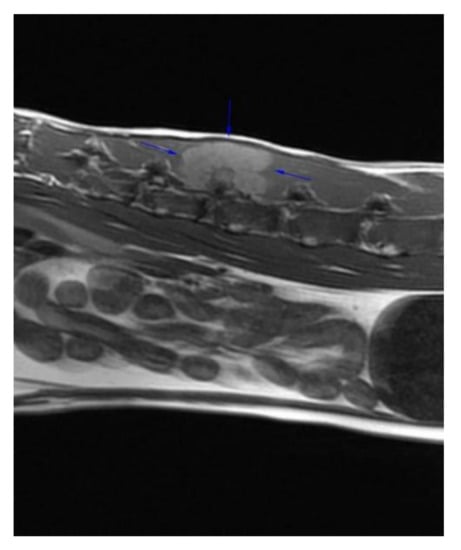

:1. Case Description

2. Materials and Methods

3. Results